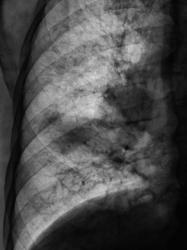

Произвели рентгенограммы в прямой и правой боковой проекциях.

Средняя доля уменьшенна в объёме, пневмония в S4.Явно изменена структура корня справа( по прямому снимку). Деформация лёгочного рисунка, не исключаеться концероматоз.Предворительно: центральный рак правого лёгкого?, осложнённый параканкрозной пневмонией в S4.Канцероматоз?? Показаны томограммы на структру корней.

Конечно налицо картина центрального рака правого главного бронха с разветвленным перибронхиальным ростом, лимфангитом справа, метастазами в лимфоузлы правого корня. Насчет параканкрозной пневмонии - неверное более справедлив термин - обструктивный пневмонит... В правом легком множественные ячеистые структуры - поликистоз.

А мне что-то видится осумкованный экссудат в горизонтальной м/долевой щели, придавливающий сверху среднюю долю. Кажется есть и диафрагмальный экссудат. Обструкции крупного бронха не вижу, правда на этих томограммах не определяется Br2. Явная патология верхней доли без уменьшения её объёма. Бронхопульмональные лимфоузлы впечатляют, а вот медиастинальные что-то не очень. Ну допустим перибронхиальный рост…, но вдоль каких бронхов?